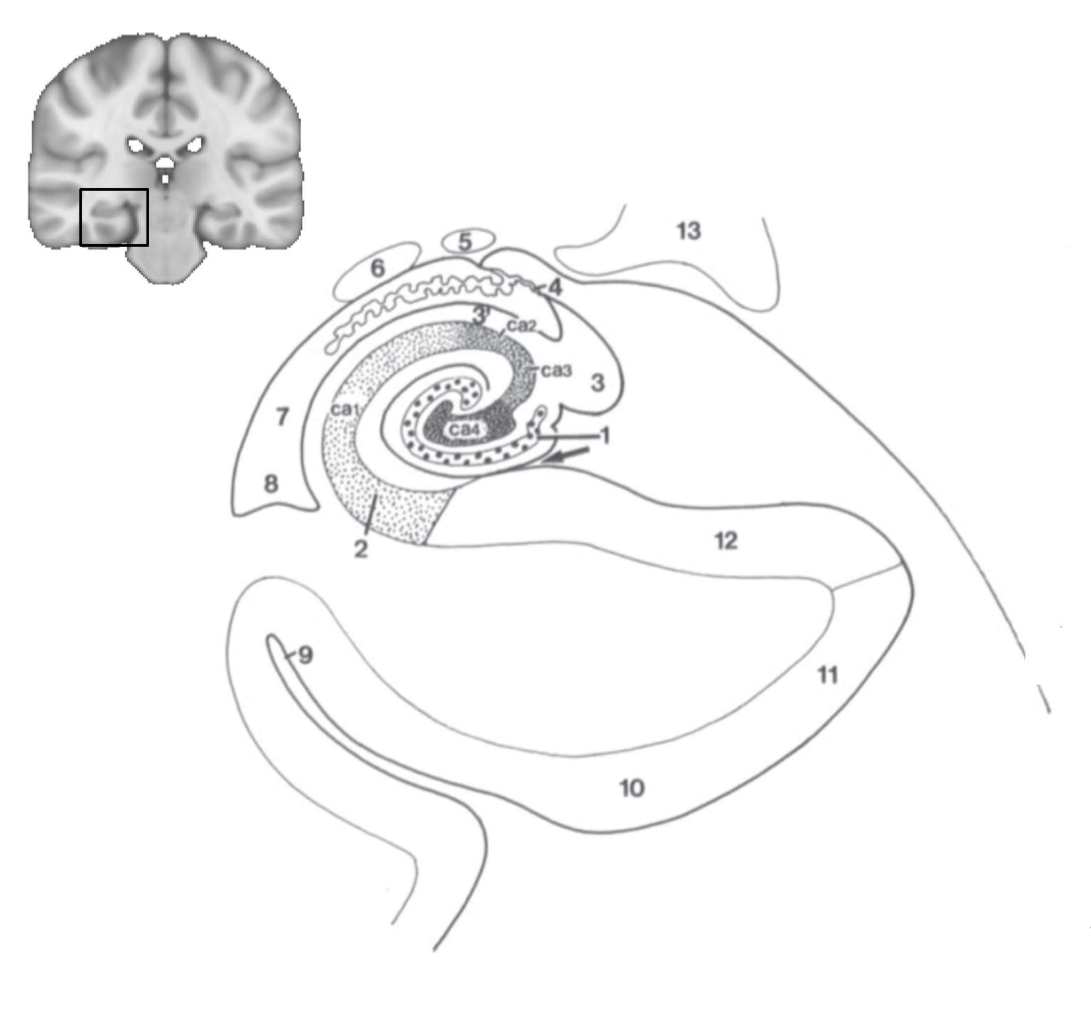

What structure is this?

hippocampus

What is 1?

hippocampus

What is 2?

rhinal sulcus

What is 3?

lateral ventricle

What is 4?

thalamus

What is 5?

entorhinal cortex

What is 6?

perirhinal cortex

What is 7?

parahippocampal cortex

What is 1?

gyrus dentatus

What is 2?

cornu ammonis

What is 3?

fimbria

What is 3’?

alveus

What is the arrow pointing to?

happicampal sulcus

What is ca1, ca2, ca3 and ca4?

fields of cornu ammonis

What is 4?

tela choroidea

What is 5?

stria terminalis

What is 6?

tail of caudate nucleus

What is 7?

temporal horn of lateral ventricle

What is 8?

collateral eminence

What is 9?

collateral sulcus

What is 10?

parahippocampal

What is 11?

entorhinal area

What is 12?

subiculum

What is 13?

lateral geniculate body